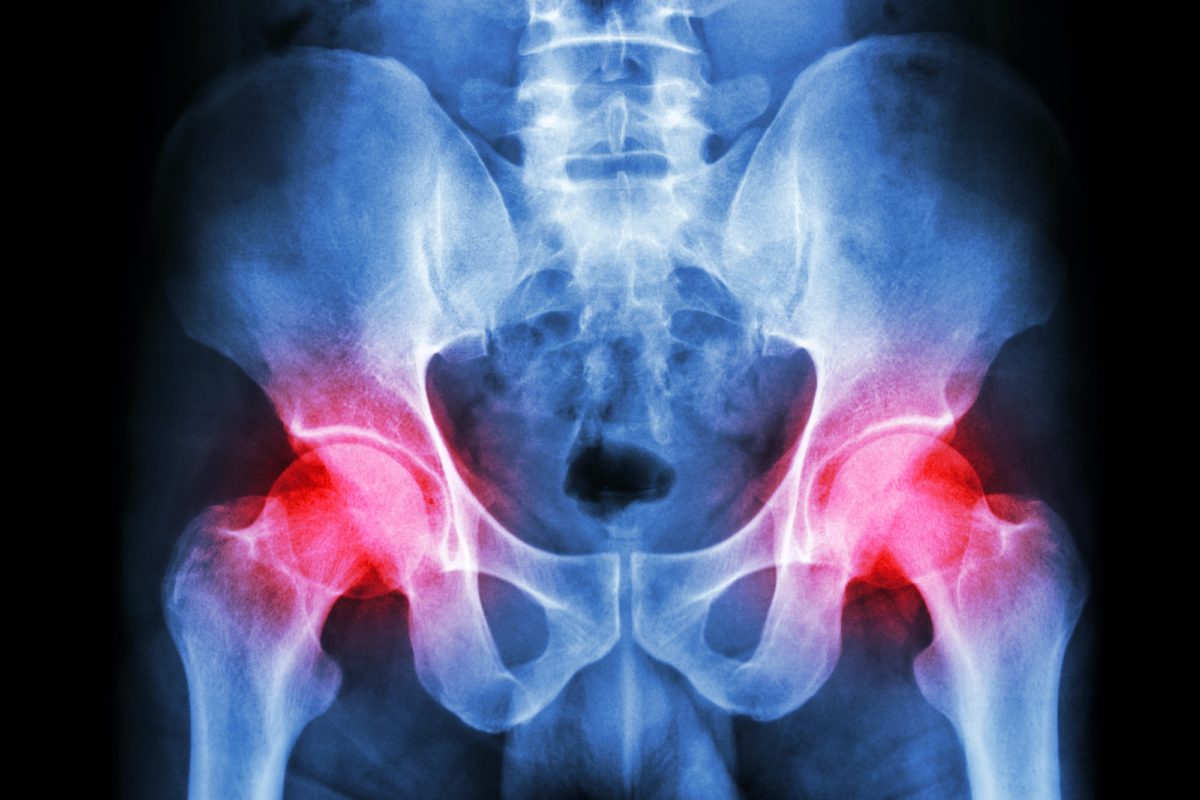

Different Causes of Pelvic Pain

When you think of pelvic pain, you may quickly associate the problem with a woman’s reproductive organs. However, pelvic pain can happen in all sexes and stem from different causes, including infections and abnormalities in internal organs. But in women, pelvic pain might be a clear indication of a problem with one of the reproductive organs in the pelvic area. When diagnosing the cause of your pelvic pain, Leela K Patel M.D. reviews your symptoms and medical history. Your doctor can also perform a physical exam and other tests to establish the cause of your pain. Below are some of the causes of pelvic pain.